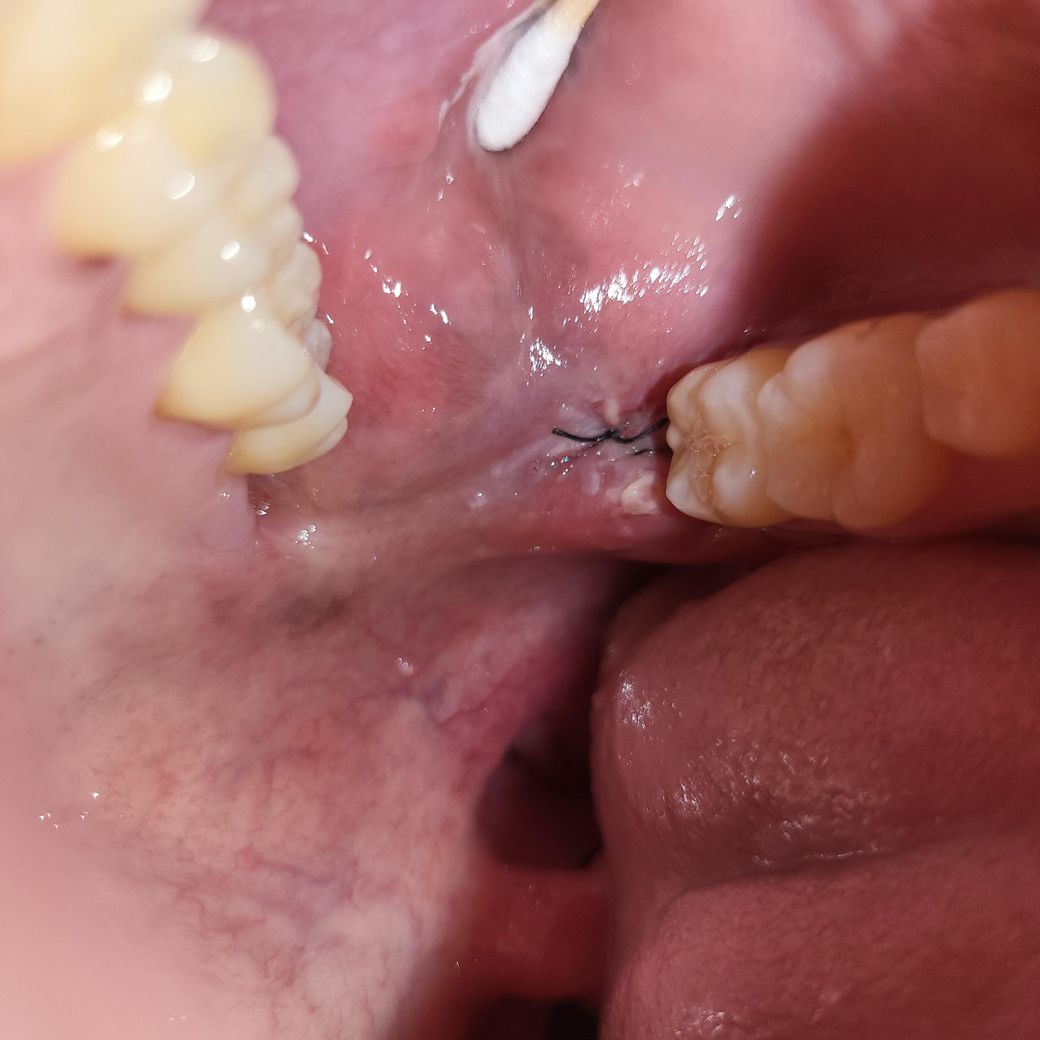

발치 부위에 하얀색 같은것이 보이는데

이거 혹시 염증이라고 볼 수 있나요?ㅠㅠ

실밥과 얽혀있는거 같기도하고

통증은 별로 없습니다.

실밥에 음식물등이 껴서 그런거니 너무 걱정하지 마세요. 사진으로 보면 잘 낳고 있는것처럼 보입니다.

하얀색으로 보이는것은 염증이 아닌것으로 보입니다.

아직 발치 후 봉합한 걸 풀지 않은 것으로 보아 발치 후 며칠 되지 않은 것 같습니다.

보통 봉합은 1주일 정도 후에 풀며, 그 동안 잇몸은 초기 치유 단계를 거칩니다

현재 사진상으로 봤을 때 잇몸은 정상 치유 과정 중에 있는 것으로 보입니다. 양치질 하실 때 물로 너무 세게 헹구시지는 마시되 해당 부위도 꼼꼼히 양치질을 해주시기 바랍니다.